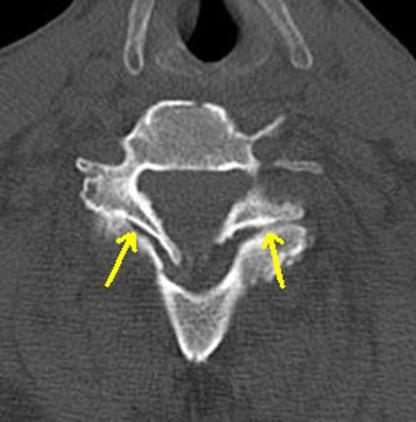

On the axial CT: Look for the Reverse Hamburger Bun Sign of the facet joints: (Case courtesy of Dr Noyan Zenger, Radiopaedia.org)

Reverse Hamburger Sign (yellow arrows)

The reverse hamburger sign:

Bilateral reverse hamburger signs.